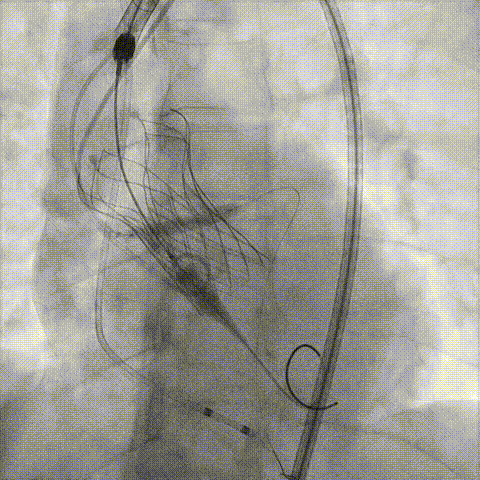

决定左冠烟囱支架保护冠脉

调整支架位置

释放冠脉支架

释放瓣膜

造影评估

支架内后扩张

冠脉造影

根部造影

最终结果